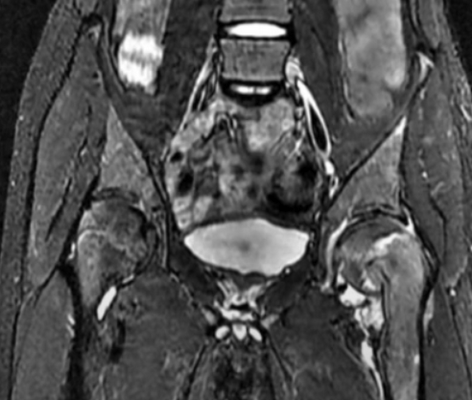

МР-скан коксофеморальных сочленений, вариант нормы

В ортопедической практике МРТ тазобедренного сустава чаще проводят для уточнения причин коксалгии - болевого синдрома в сочленении. Способ исследования не подразумевает использования ионизирующего излучения, что особенно актуально для детей и беременных женщин. Процесс создания четких снимков, которые можно увеличивать, рассматривать в объемном виде, базируется на использовании магнитного резонанса и компьютерных технологий. Для улучшения возможностей визуализации применяют контрастирование. Диагностическая ценность фото, полученных после введения гадолиния, сопоставима с результатами артроскопии - инвазивного исследования с проникновением в полость сочленения хирургических инструментов.